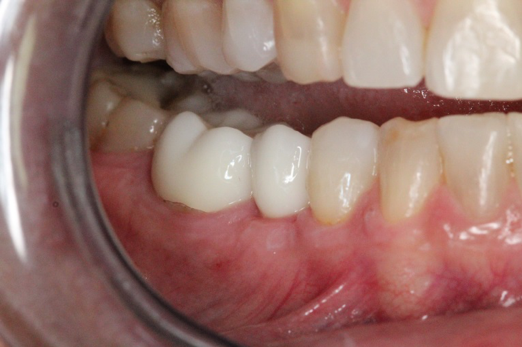

Fig 16. Final restorations (15 weeks postoperatively).

Figure 16

After the preparations were evaluated and accepted by the clinician, provisionals were completed with traditional crown-and-bridge techniques. Then the provisionals were fabricated with a replication stent derived from the diagnostic wax up (Figure 14). The provisionals were well-fitted to both the natural dentition and the ceramic dental implants (Figure 15). The provisional that was fixed to the implant was kept out of occlusion and had a narrow buccal-lingual occlusal table. The smaller occlusal table and short occlusal scheme provided light loading forces and stimulated the bone tissuethe brain detects the stimuli and sends osteoblasts to the area to increase bone density surrounding the implant. The recommendation for the light-loading provisional phase was to have the patient function with the provisionals for 4 weeks.

The final impression appointment follows the light-load phase, provided the implant is stable and the soft tissue is acceptable to the clinician. Polyvinyl putty and light-body impression materials were used in this case; analog casts and final full-zirconia full crowns were fabricated (Figure 16). The patient provided feedback that chewing was comfortable and without food impactions. Keratinized gingival cuff was developed, and natural-tooth contours for the restorations mimicked what is normally found in human dentition. The healed bone surrounding the ceramic dental implant was similar in density and crestal levels in comparison with the adjacent natural teeth, evident in the radiographic evaluation (Figure 17). Final long-term restorations at the gingival crest and restoration interfaces were also consistent in optimum periodontal health and gingival height. Arch-form integrity was upheld and occlusion was managed; osseointegration and light-load principles optimized the success of the restorations, and an acceptable, harmonious esthetic outcome was achieved for the patient.